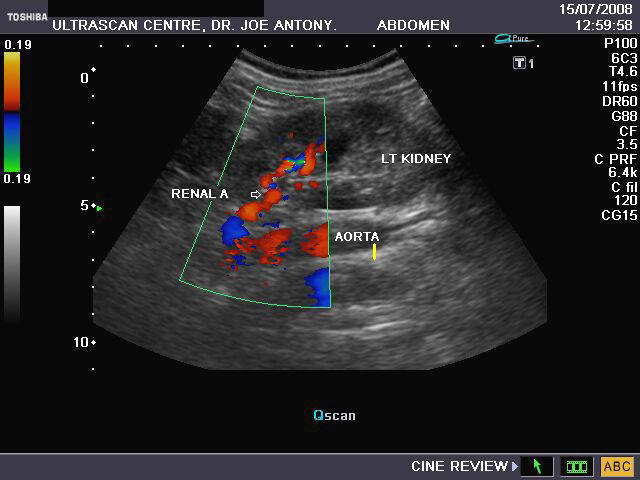

Ultrasound Imaging

Ultrasound imaging uses pulses of high-frequency sound to create real-time images of soft tissues and blood flow.